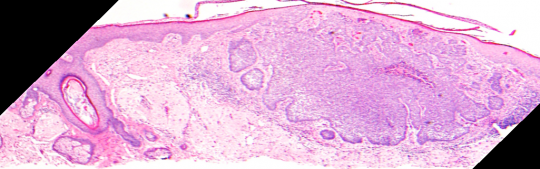

VA54: Left Superior Temple, Basal Cell Carcinoma, Nodular

- * denotes area of liquifactive necrosis with remnant necrotic cell debris